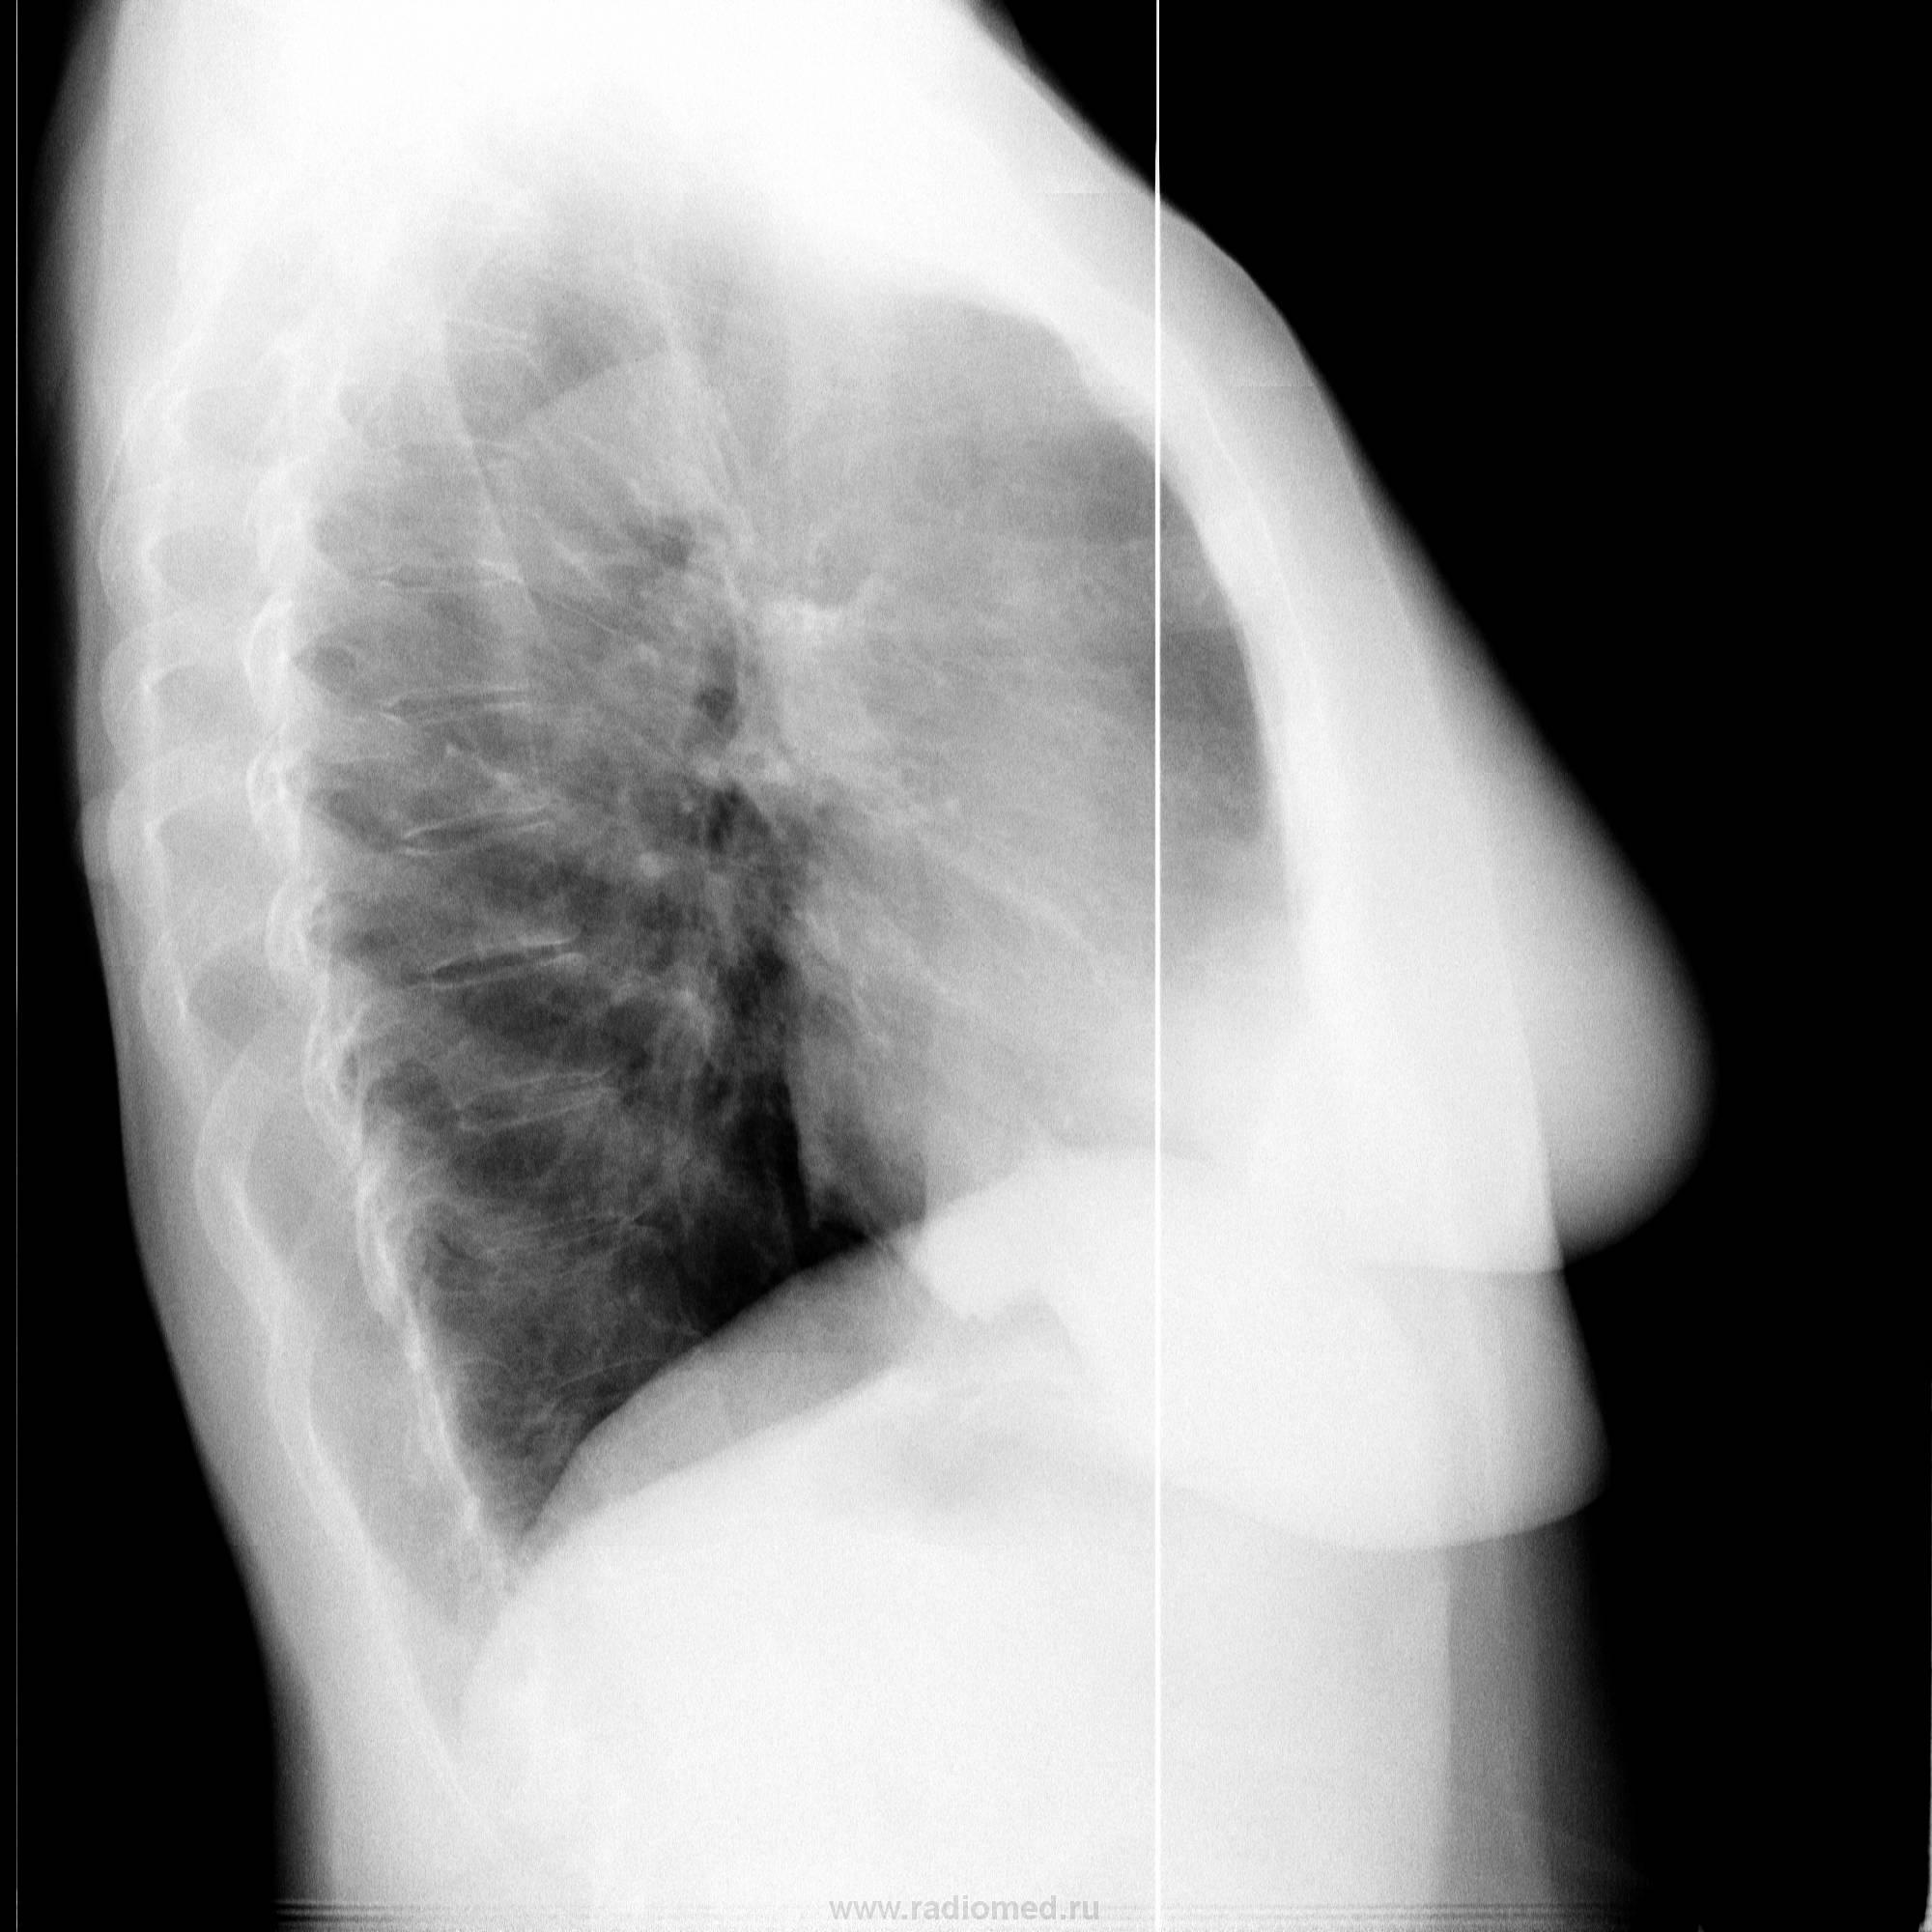

Женщина. Из другой страны. У родственников в гостях. Решила пройти ФГ. Что скажете, коллеги?

Конечно, как без боковых))))

Та, "ОНО" же сзади, на фоне "мягких тканей"

Новообразование на коже спины, на короткой ножке, внешне не изменено, некоторое покраснение кожи вокруг.

К чести моих лаборантов сказать, "воевали" они вчера с этим образованием без меня (сдавал годовой отчет), но все осмотрели, ощупали, даже пытались вывести на контур, что, с некоторыми оговорками, можно им зачесть)))

Отличные снимки, адекватные физико-технические условия "съёмки", ч то свидетельствует и о профессиональном уровне лаборантов. Что случай отличный указывал уже выше, НО хочу добавить, что именно Вами, случай преподнесен максимально корректно.

Гомогенность и четкость при полной индиферентности окружающей легочной ткани говорит о доброкачественности, так что опытного рентгенолога на мякине не проведешь, даже без бокового. Но при желании попить финансов с пациента можно крутить на КТ, МРТ и т.д., лишь бы бабок хватило.